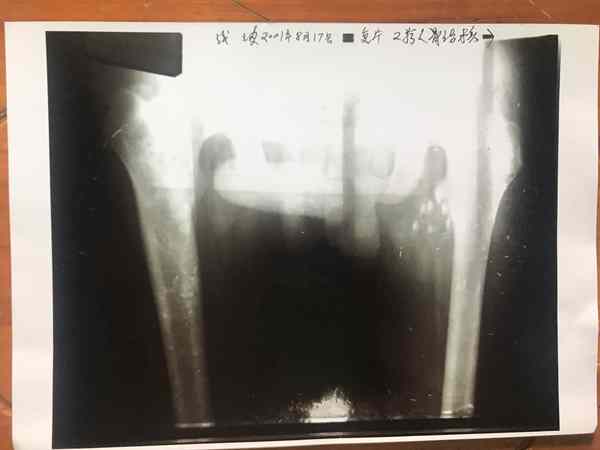

2、非手术治疗:骨结核,股骨头坏死,骨伤后,骨质不长,《骨细胞可快速生长》。目前在医学界还没有发现治疗骨病这种速度,请看下面图片检查结果对比。颈椎病引起的头昏,头痛、腰椎病,腰椎手术后遗症,一至2天见效。